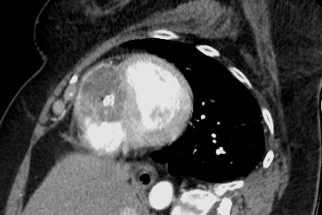

A female patient in her 60s has been followed up with annual chest-abdominopelvic computed tomography (CT) due to a clinical history of extraskeletal mesenchymal chondrosarcoma with disseminated metastatic disease. She was previously submitted to various surgical treatments, namely excision of the primary lesion located on the left thigh thirteen years before, as well as bilateral pulmonary and colic metastasectomy, left adrenalectomy and nephrectomy, splenectomy and caudal pancreatectomy in 2019. In a routine contrast-enhanced thoraco-abdominopelvic CT, a round, solid mass was found with heterogeneous attenuation, as well as internal calcifications, occupying most of the right ventricular chamber, due to heart metastasis from extraskeletal mesenchymal chondrosarcoma. It involves the right apex and almost two thirds of the ventricular septum, causing discrete bulging to the left.(Figs. 1, 2 and 3)

Figure 1: Axial contrast-enhanced CT image reveals a round, solid mass, with heterogeneous attenuation, as well as internal calcifications, occupying most of the right ventricular chamber, due to heart metastasis from extraskeletal mesenchymal chondrosarcoma. It involves the right apex and almost two thirds of the ventricular septum, causing discrete bulging to the left.

Figure 2: Coronal contrast-enhanced CT image shows the same round, solid mass, with heterogeneous attenuation, as well as internal calcifications, occupying most of the right ventricular chamber, in this image being more evident its apical location, as a result of heart metastasis from extraskeletal mesenchymal chondrosarcoma.